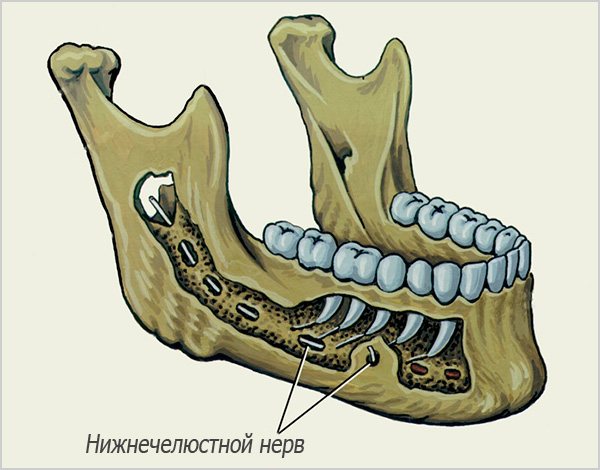

Повреждение стенки нижнечелюстного канала и нервов нижней челюсти

Данное осложнение во время имплантации зубов не всегда имеет длительные негативные последствия, так как, несмотря на пугающее название, на самом деле проявляется обычно лишь онемением на нижней челюсти (чаще всего немеют губы). Даже без лечения эти симптомы могут самостоятельно проходить в течение 2-3 недель, максимум – 2-3 месяцев.

Кроме того, стоит иметь в виду, что чувство онемения на соответствующей стороне лица может быть также следствием сдавливания нерва в нижнечелюстном канале. Это иногда происходит вследствие кровотечения в костномозговых пространствах – кровь может выходить не только в сторону полости рта, но и постепенно двигаться по пространствам кости, ведь внутрикостная ткань челюсти не «цельнолитая», а ячеистая. Попадание даже сравнительно небольшого количества крови в область прохождения нижнечелюстного нерва в канале создает временное сдавливание. Постепенно кровяные массы рассасываются, но нужно время, когда нерв восстановится от такого сдавливающего воздействия (обычно не более 5-7 суток).